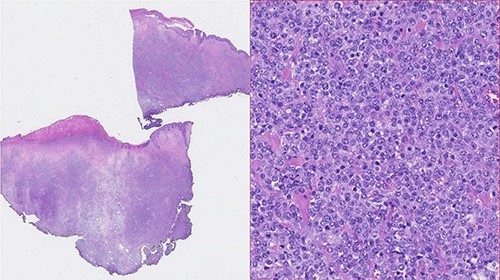

A 73-year-old Caucasian man with a history of hypertension, atrial flutter and Type 2 diabetes mellitus underwent left inguinal hernia repair by Rutkow-Robbins hernioplasty in 2017 without immediate surgical or postoperative complications. In 2021, he reports the appearance of a painless swelling in the left inguinal scar. The patient was medicated with antibiotics without improvement and was sent to the General Surgery consultation with the diagnosis of inguinal mesh rejection. Upon observation by General Surgery, the patient had an ulcerated area of the medial portion of the scar, measuring 1 × 2 cm, with drainage of seropurulent content and surrounding erythema, interpreted as the external orifice of a fistulous tract. The diagnosis of late mesh rejection was maintained, and the patient underwent prosthesis removal without hernia repair. During surgery, extensive peri-mesh fibrosis was found but without apparent signs of infection. The scar was removed en bloc including the ulcerated area and sent for anatomopathological examination. The surgery was uneventful and the patient was discharged. Histological examination (Figs 1–3) revealed extensive involvement of the dermis and hypodermis by a high-grade non-Hodgkin lymphoproliferative process with characteristics of diffuse large-cell B lymphoma, which focally conditions epidermal ulceration. The immunohistochemical study showed diffuse staining for CD20, MUM-1 and CD10, with weak and heterogeneous staining in ~40–50% of neoplastic cells for C-MYC and 80–90% of the same population cell for Ki-67. Immunostains for CD30 were not observed and with anti-CD3 and anti-CD5 antibodies, only marking of scattered rare reactive T lymphocytes was observed. Finally, the neoplastic cell population had no staining for bcl2, but diffuse staining for bcl6. Upon reassessment, the patient had wound dehiscence with an extensive ulcerated area (Fig. 4) and was oriented to hematology. Bone marrow biopsy, myelogram and flow cytometry were normal and computerized tomography of the neck, chest, abdomen and pelvis revealed a right inguinal adenopathy (Fig. 5). The patient was staged as IIa and proposed for systemic treatment with rituximab, cyclophosphamide, doxorubicin, vincristine and prednisolone (R-CHOP).

Photomicrographies. Lymphoid infiltrate immunophenotype, with a diffuse expression of CD20, bcl6, C-Myc (upper half from left to right), and Ki67, MUM1 and CD10 (lower half from left to right).